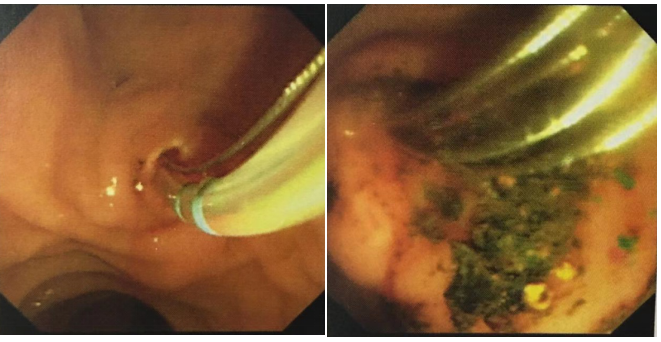

北京市垂杨柳(微创)医院微创肝胆外科团队在王永光院长和蒋圣军主任的带领下,反复对患者病情和身体情况进行研究后,并与患者及家属进行深入沟通,认为在SpyGlass直视下U100冷激光碎石取石手术碎石取石为创伤和风险最小的治疗方案。术中只需十二指肠乳头小切开,尽可能保护十二指肠乳头肌功能,较传统ERCP切口较大、对十二指肠乳头损伤较大等,具有明显优势。患者胆管下段结石嵌顿,使用U100冷激光碎石对于周围正常胆管组织损伤较小,直视下碎石精准确切,碎石后使用取石网篮取出较大结石,可以避免“石街”形成及小结石淤积。术后应用胆汁酸类药物治疗,利于胆汁排泄,冲刷胆道内残余结石粉末,避免结石复发。

北京市垂杨柳(微创)医院微创肝胆外科蒋圣军主任介绍说,采用SpyGlass系统直视下使用U100冷激光碎石治疗胆总管较大结石的方法,安全、高效,可明显提高巨大胆总管结石的碎石效率及一次性取石成功率。中国胆管结石的发病率在世界范围内较高,而在国际上现有治疗胆管结石的方法中,Spyglass引导下的U100冷激光碎石术是效果最好的一种,可广泛适应于各类胆道结石患者,包括胆囊结石、胆总管结石和肝内胆管结石的治疗。